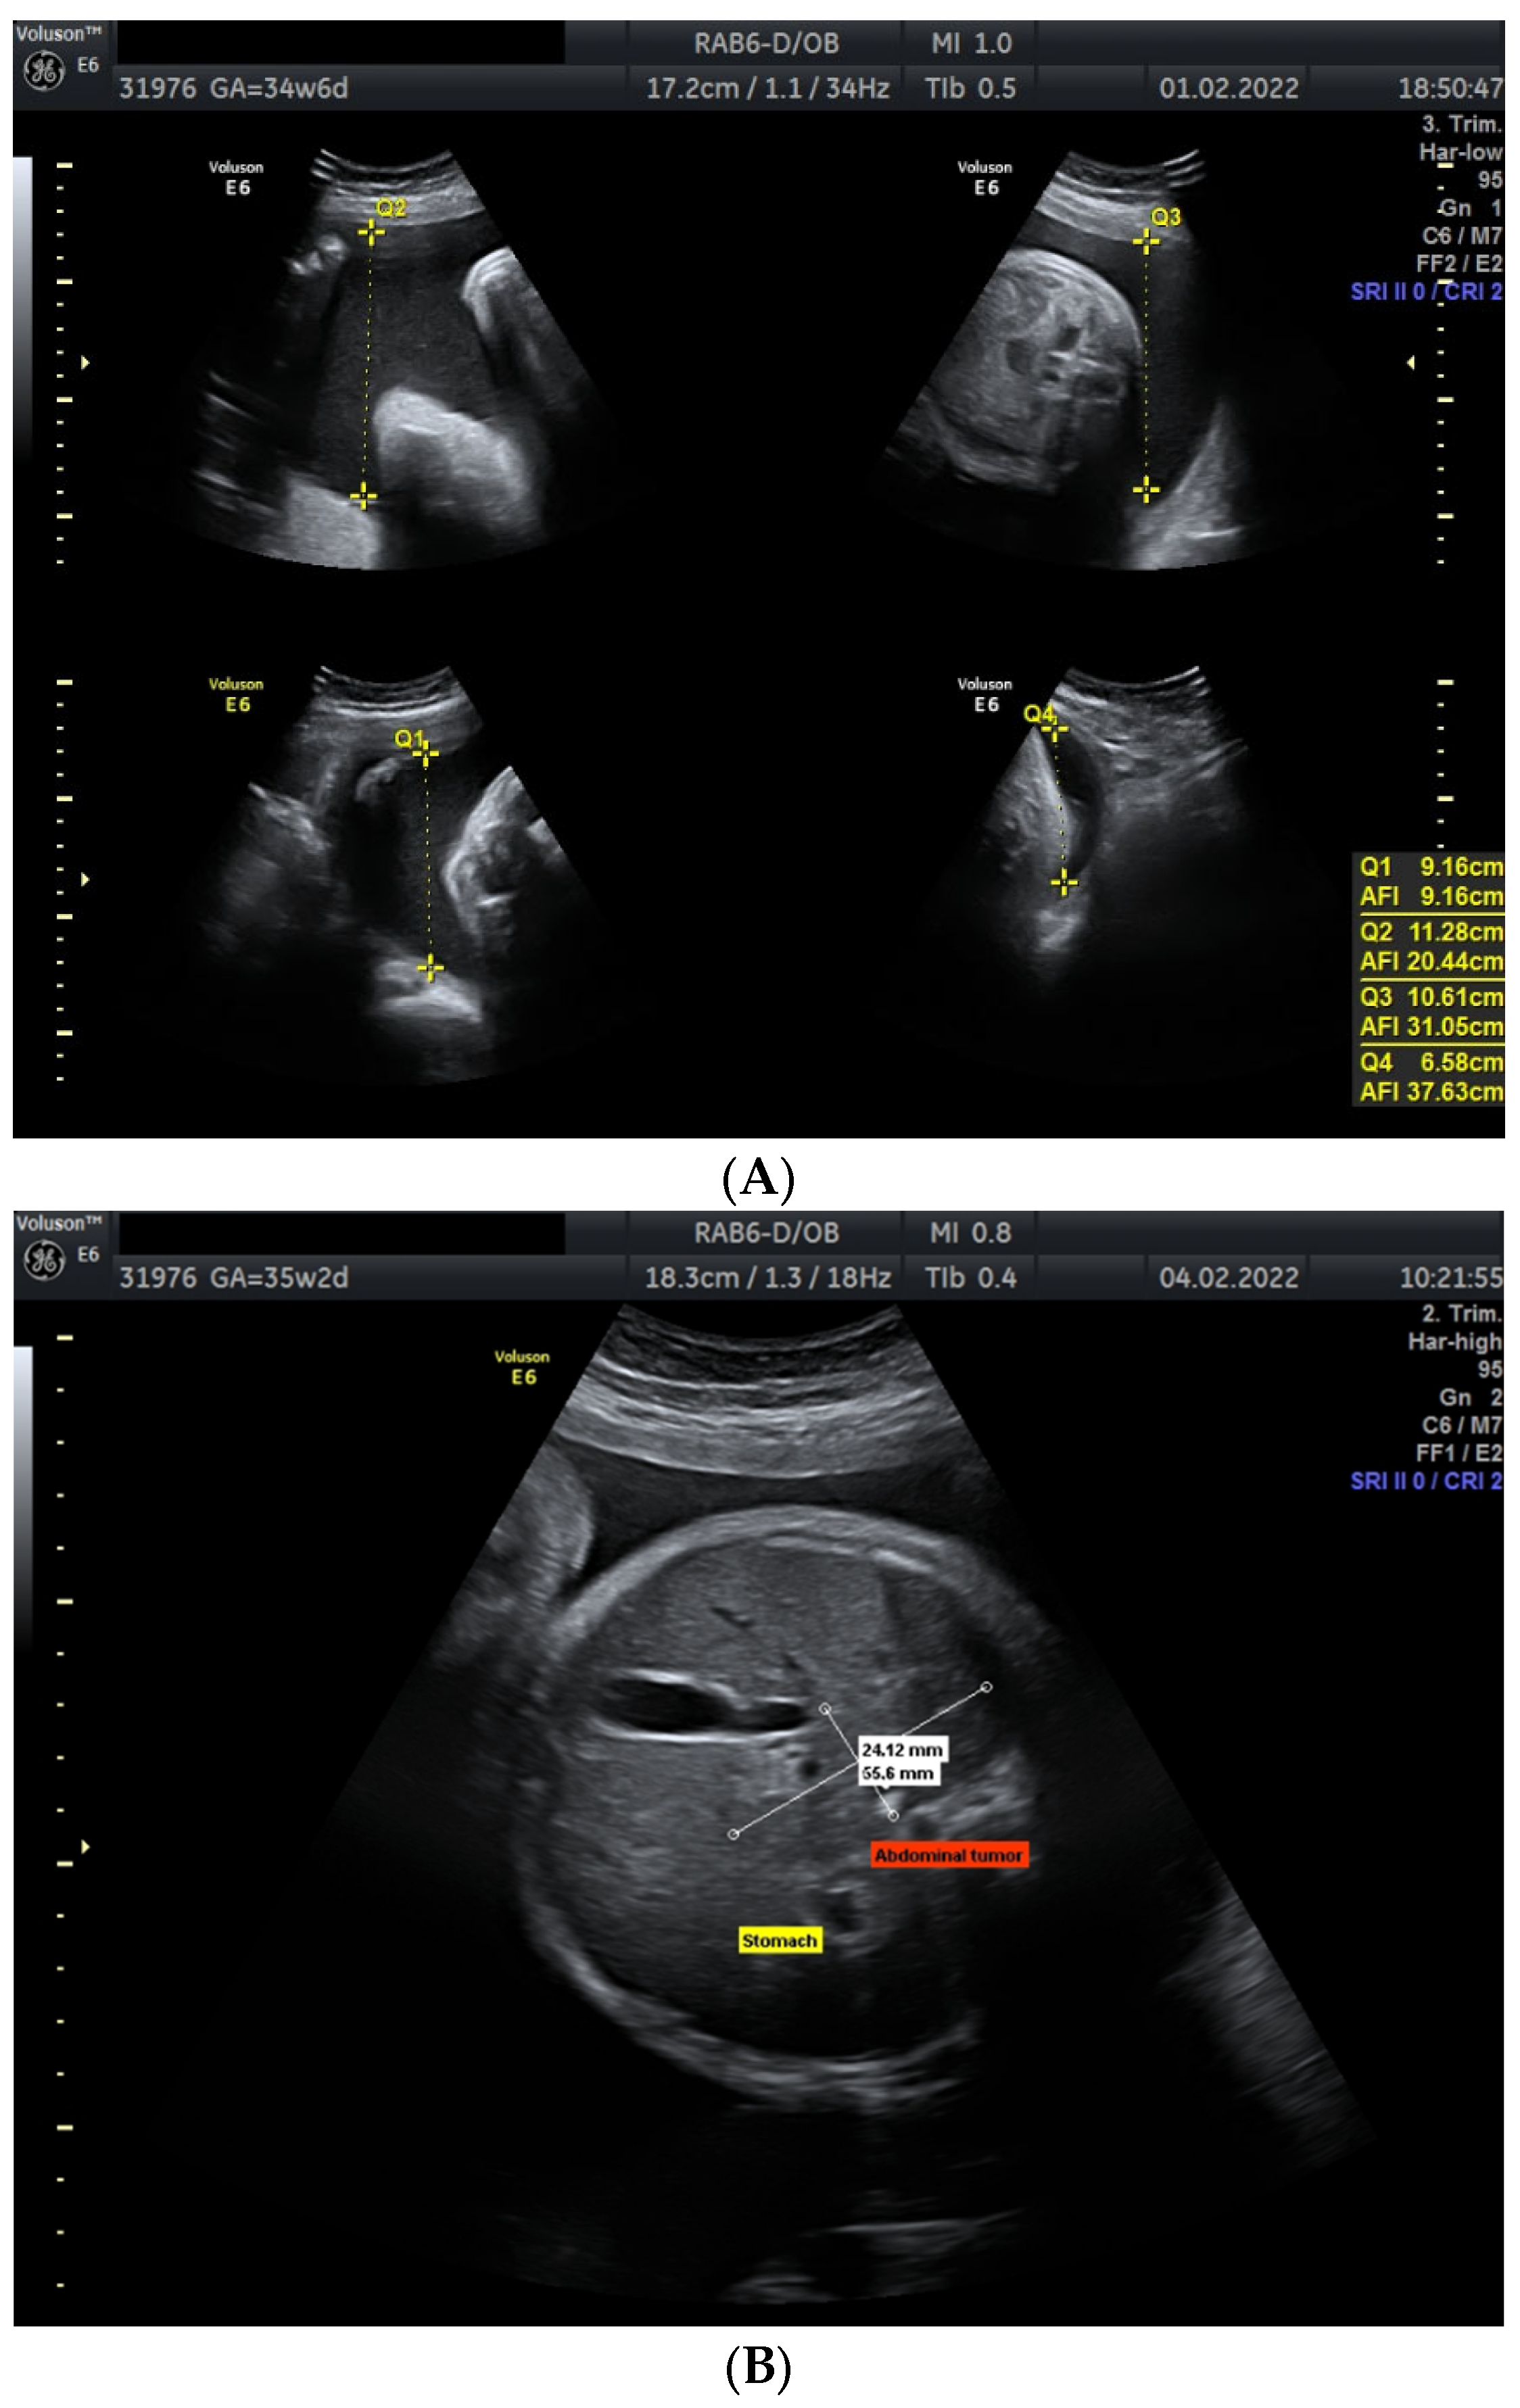

3. Case Presentation